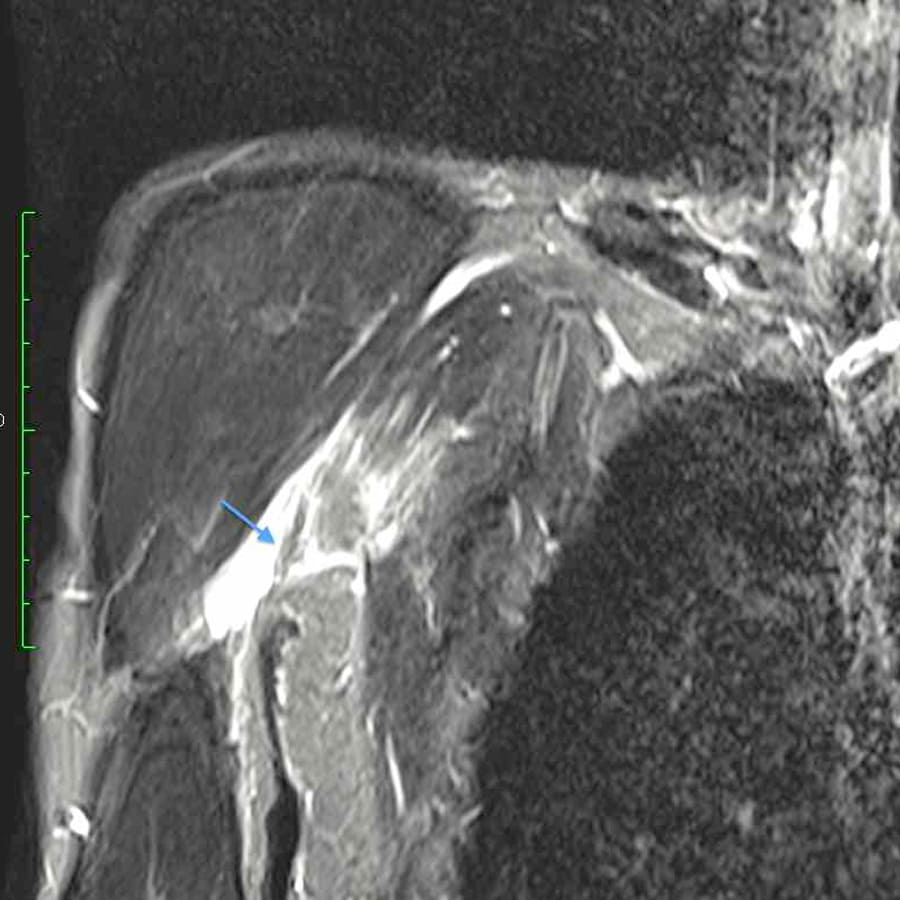

A avaliação clínica feita por um ortopedista especialista em ombro, cotovelo e medicina esportiva é fundamental. Muitas vezes, apenas o exame físico já aponta o grau da lesão. Contudo, para confirmação, a ressonância magnética e/ou a ultrassonografia musculoesquelética podem ser solicitadas.